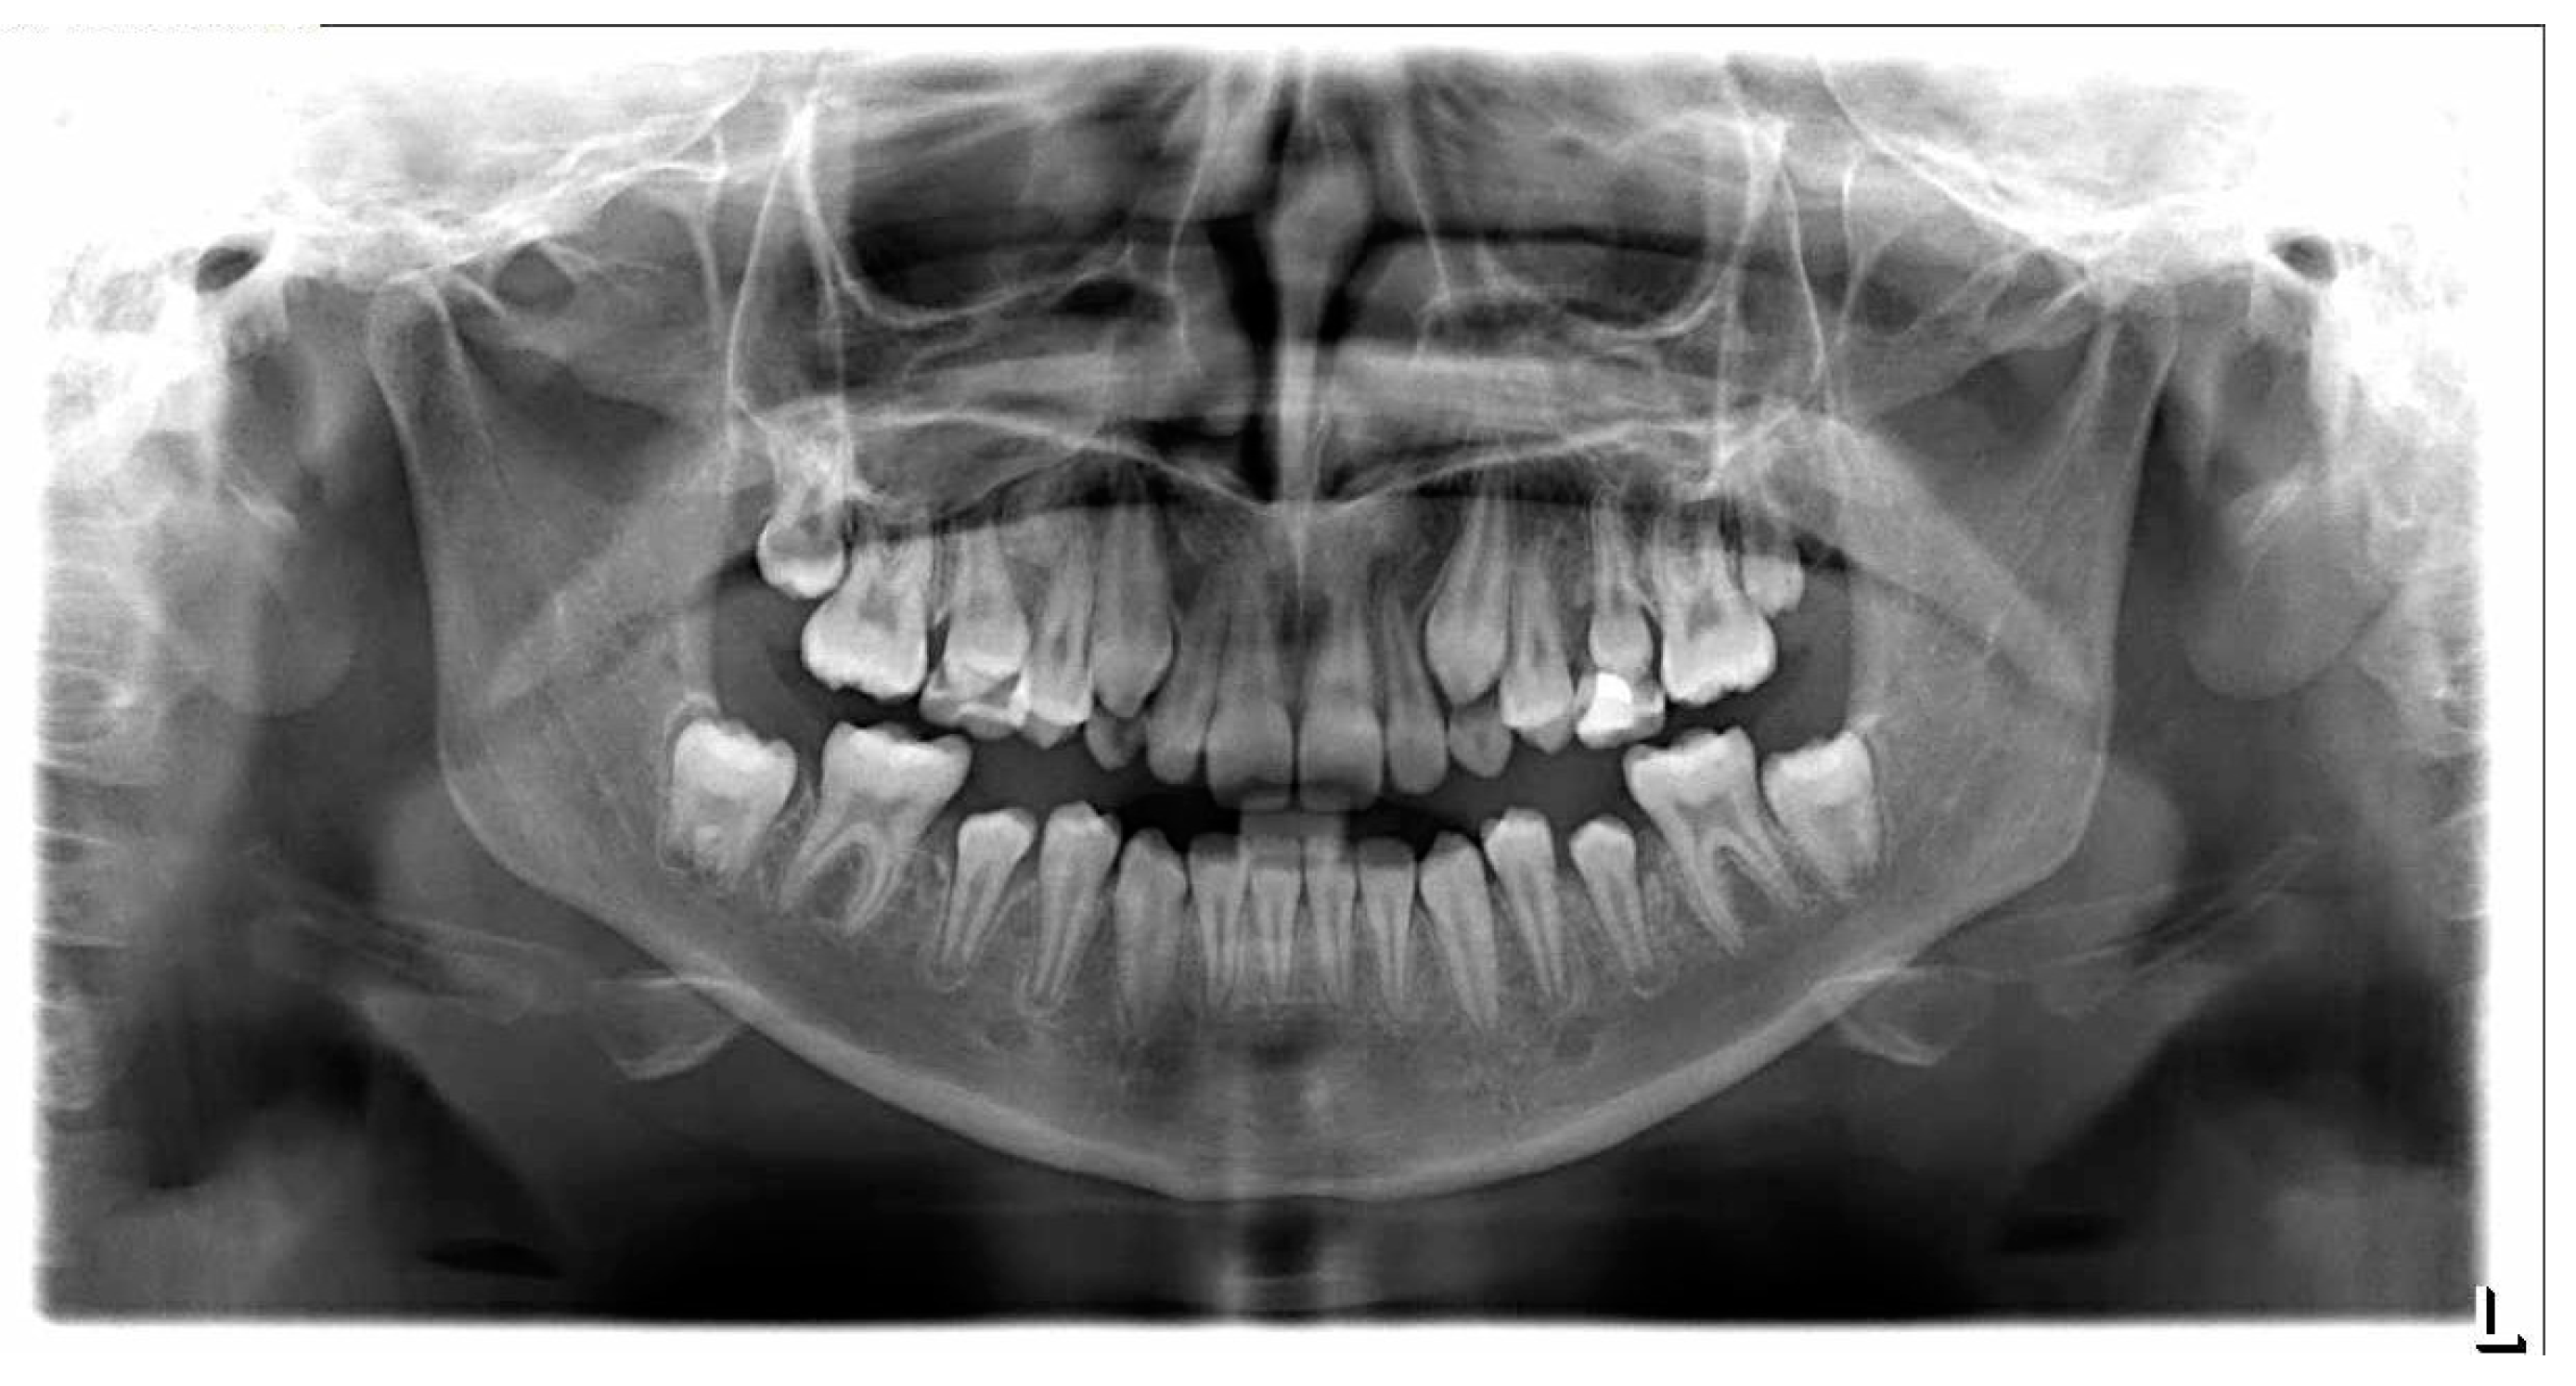

3. Results